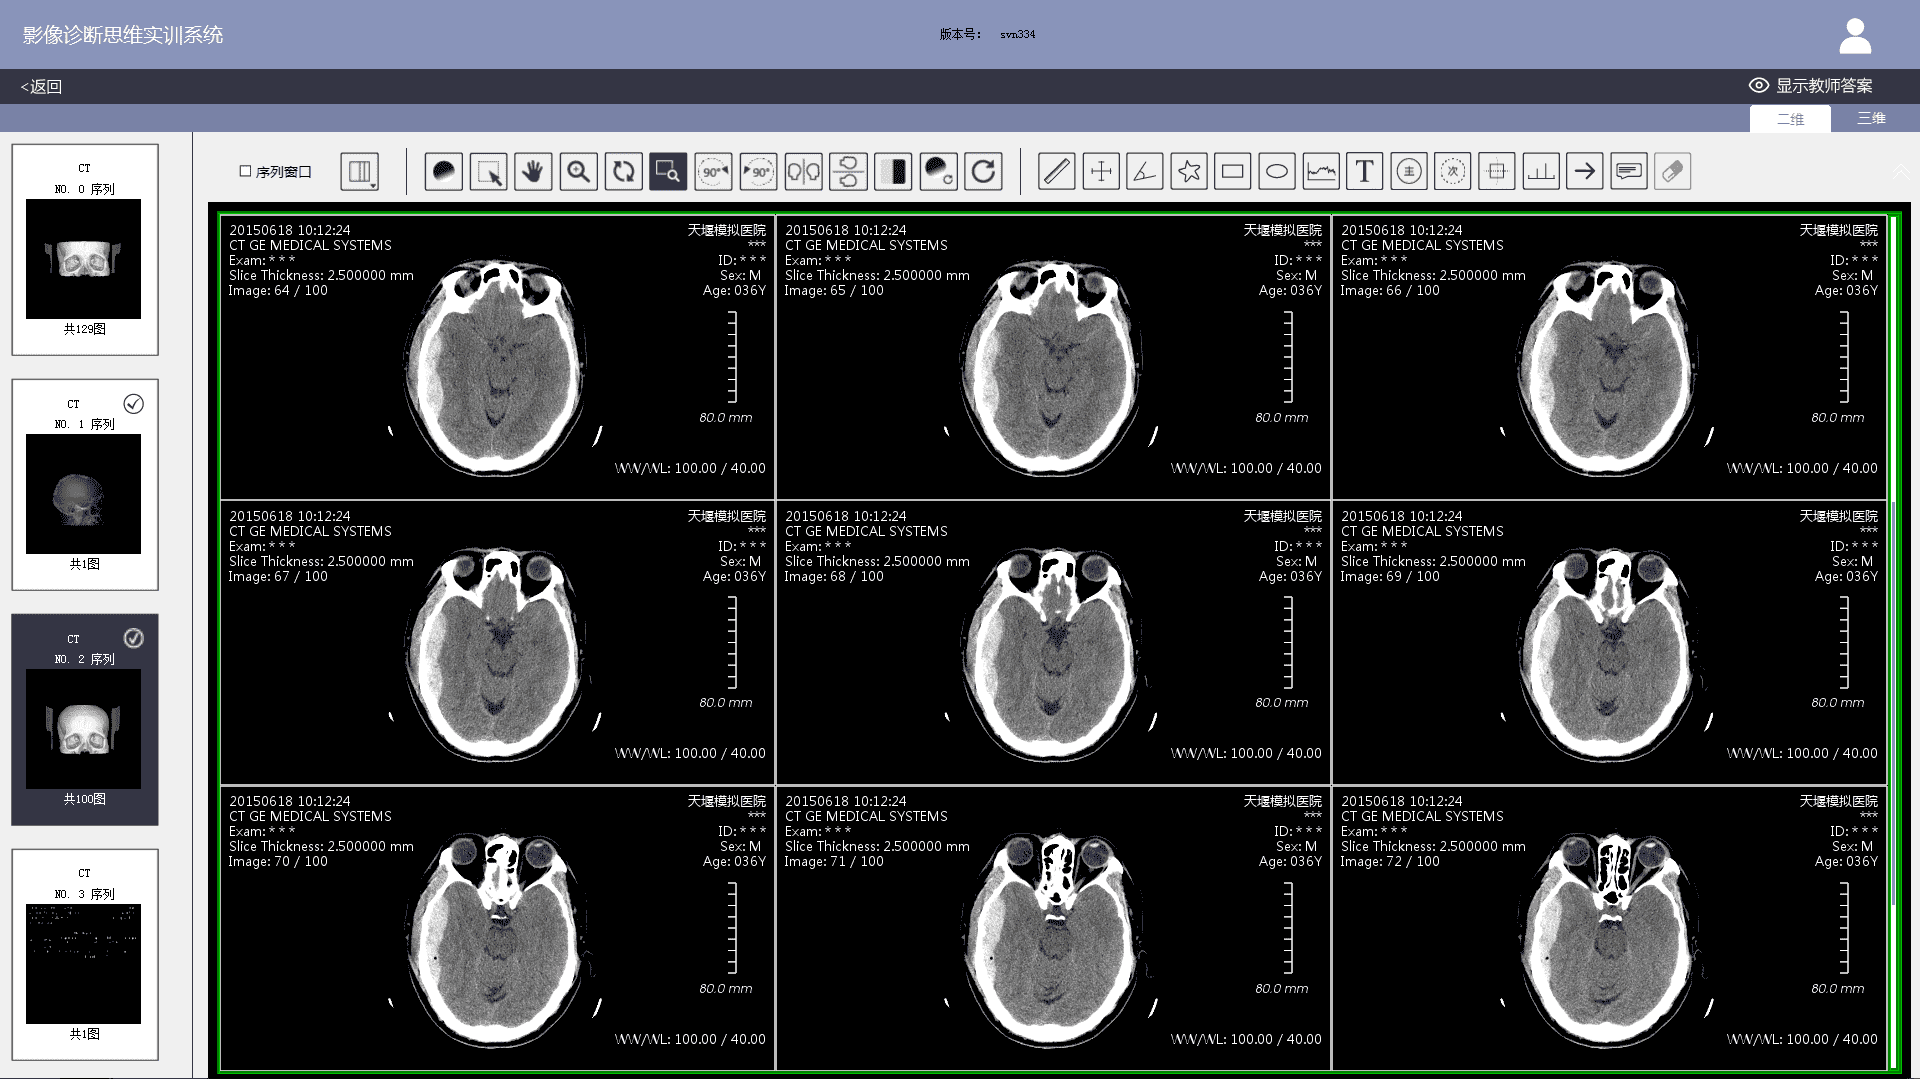

3) Imaging workstation: The system comes with an imaging workstation and all cases can be loaded with DICOM files. Teachers can post-progress them according to actual teaching needs. The post-processing function meets the basic requirements of a common clinical imaging workstation, including: 1) layout. Users can choose 1X1, 1X2, 2X1, 2X2, 2X3, 3X3, etc.; 2) Window width and level adjustments; 3) Zoom in and out; 4) Zoom in on the area of interest; 5) Left turn 90 degrees; 6) Right turn 90 degrees; 7) Left and right mirror flip; 8) Up and down mirror flip; 9) Negative film; 10) Distance measurement; 11) Two-way ruler; 12) Angle measurement; 13) Polygon measurement; 14) Adding notes & comments; 15) Labeling major signs; 16) Labeling secondary signs, etc.

3) When viewing case images, students can post-process DICOM files on the imaging workstation to observe positive and negative imaging signs in greater detail. After finishing a case exercise, student's test results, the correct diagnosis report and the comparison of the thinking processes will show. Students can also participate in image thinking case assessment set up by teachers.